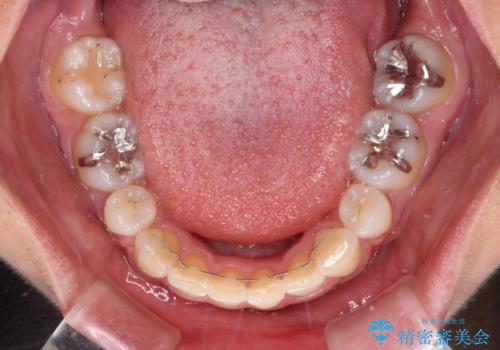

デコボコで飛び出した前歯 ワイヤー装置による抜歯矯正

矯正治療前の咬み合わせで、前歯がすり減ってしまい、歯列が整ったときに先端がガタガタになってしまったため、矯正治療後に形態修正を行いました。